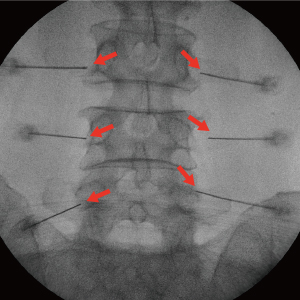

Treatment until the last painC-arm(특수영상치료장치)을 보며 치료하는 척추 비수술치료로 척추의 신경을 둘러싸고 있는 경막 바깥쪽에 약물을 투입하는 시술입니다. 허리 또는 목의 손상된 척추 부위에 가는 바늘을 통해 직접적으로 약물을 투입함으로써 신경 주위 염증과 부종을 가라 앉히며, 자율신경계의 정상적인 반응을 유도하는 치료입니다.

국소마취 하 디스크와 신경 사이에 정확히 바늘을 삽입하여 신경을 안정시키고 염증을 완화시킵니다.